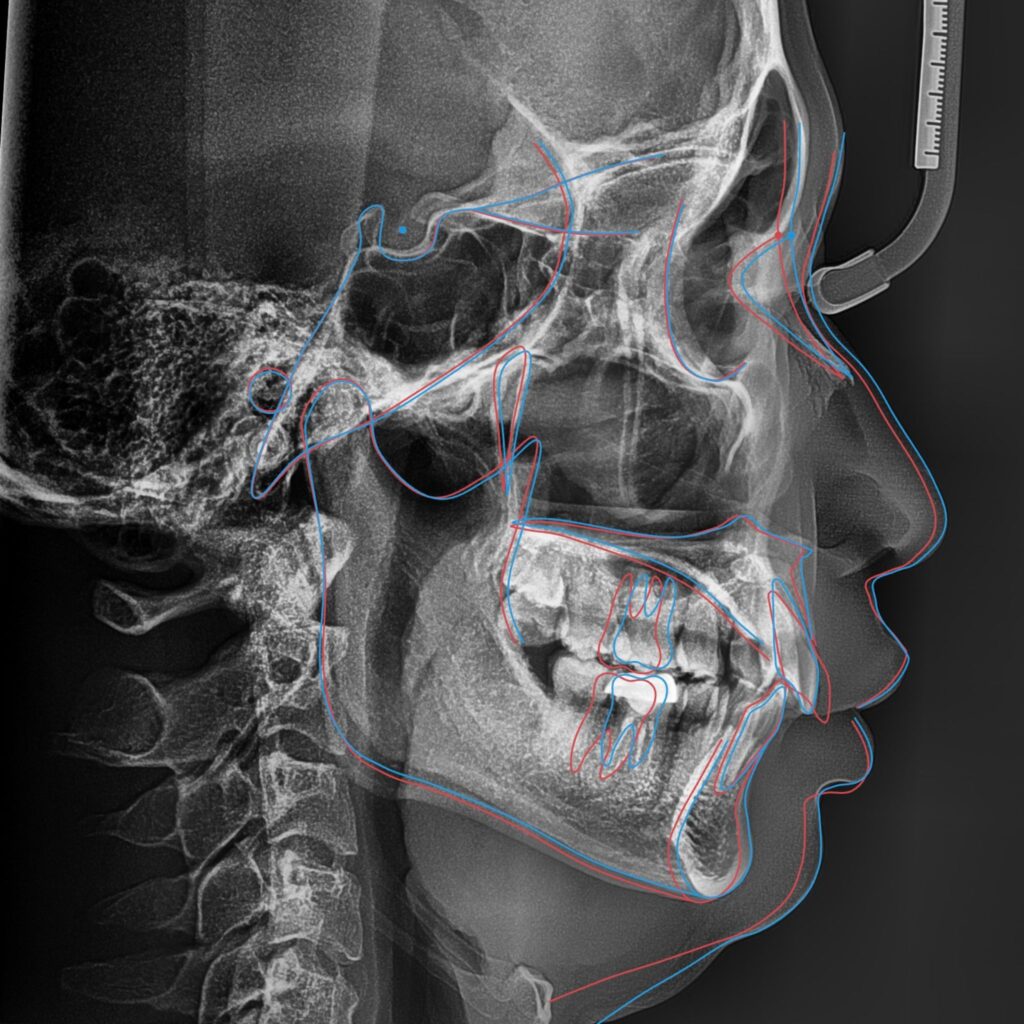

Trên mô phỏng, đây được xem là một ca niềng răng có tiên lượng tốt. Tuy nhiên, sau 2,5 năm điều trị, kỹ thuật chồng phim (superimposition) cho thấy phản ứng sinh học thực tế của cơ thể khác biệt so với dự đoán ban đầu.

III. Răng ngầm – yếu tố then chốt thay đổi toàn bộ kế hoạch niềng răng

1. Răng ngầm và giới hạn dịch chuyển răng cửa

Nguyên nhân chính khiến kết quả thực tế không đạt như VTO là sự hiện diện của một răng ngầm tại vị trí chân răng 11. Răng này mọc theo hướng từ ngoài vào trong và nằm sát lỗ thần kinh ống răng cửa – một cấu trúc giải phẫu nhạy cảm.

Răng ngầm trở thành rào cản sinh học khiến việc kéo răng cửa vượt quá giới hạn an toàn là không thể.